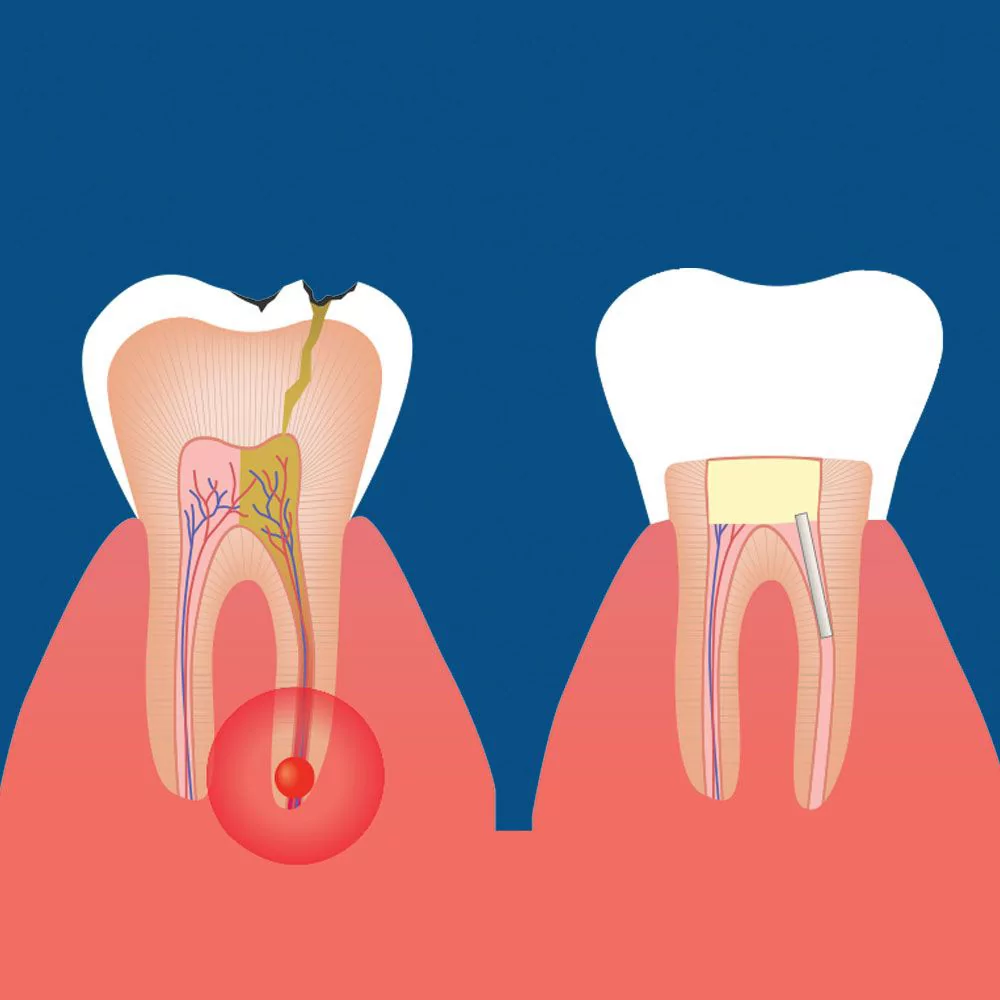

Root canal treatment, also known as endodontic therapy, is a procedure performed to treat the inside of the tooth when its pulp becomes infected or inflamed. The pulp, located in the center of the tooth, contains nerves, blood vessels, and connective tissue. When it becomes infected due to deep decay, trauma, or a crack in the tooth, it can lead to severe pain and swelling if left untreated.

- An abscess (or pimple) on the gums.

In a root canal procedure, the pulp of the tooth (the living tissue inside) is removed and the resulting space is filled with special, medicated dental materials that restore the tooth to full function. Using root canal therapy not only preserves your natural tooth, extending its lifetime, restoring functionality and it also protects and preserves the jaw bone and other supporting tissues around the tooth. Wherever possible, saving your natural tooth will also save you from more pain and expense down the road.